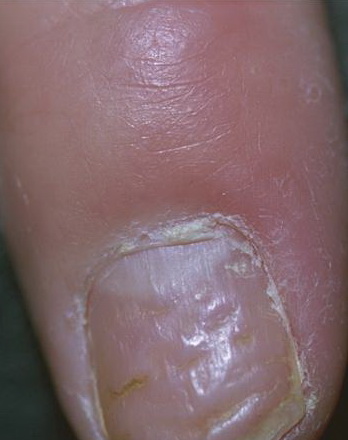

Psoriasis can be limited to the nails and produce nail signs that mimic those of a large number of other nail disorders. Pitting is considered by dermatologists to be the typical symptom of psoriasis. Psoriatic pits are limited to the fingernails, are large, deep, and irregular , and represent psoriatic involvement of the proximal nail matrix.

Onycholysis, salmon patches, and subungual hyperkeratosis are additional clinical signs of nail bed psoriasis. Onycholysis is actually the most common manifestation of nail psoriasis and may affect both fingernails and toenails. In fingernails the presence of an erythematous border along the onycholytic area is diagnostic for nail psoriasis . In toenails onycholysis is usually combined with subungual hyperkeratosis and may closely resemble onychomycosis.

Salmon patches (oil drop sign) are also diagnostic for nail psoriasis. They are seen in fingernails and appear as yellow-red areas of discoloration in the center of the nail or bordering an onycholytic area . Rarely, nail psoriasis may produce severe nail plate abnormalities such as trachyonychia or crumbling. Other common but rather aspecific signs include splinter hemorrhages and paronychia.